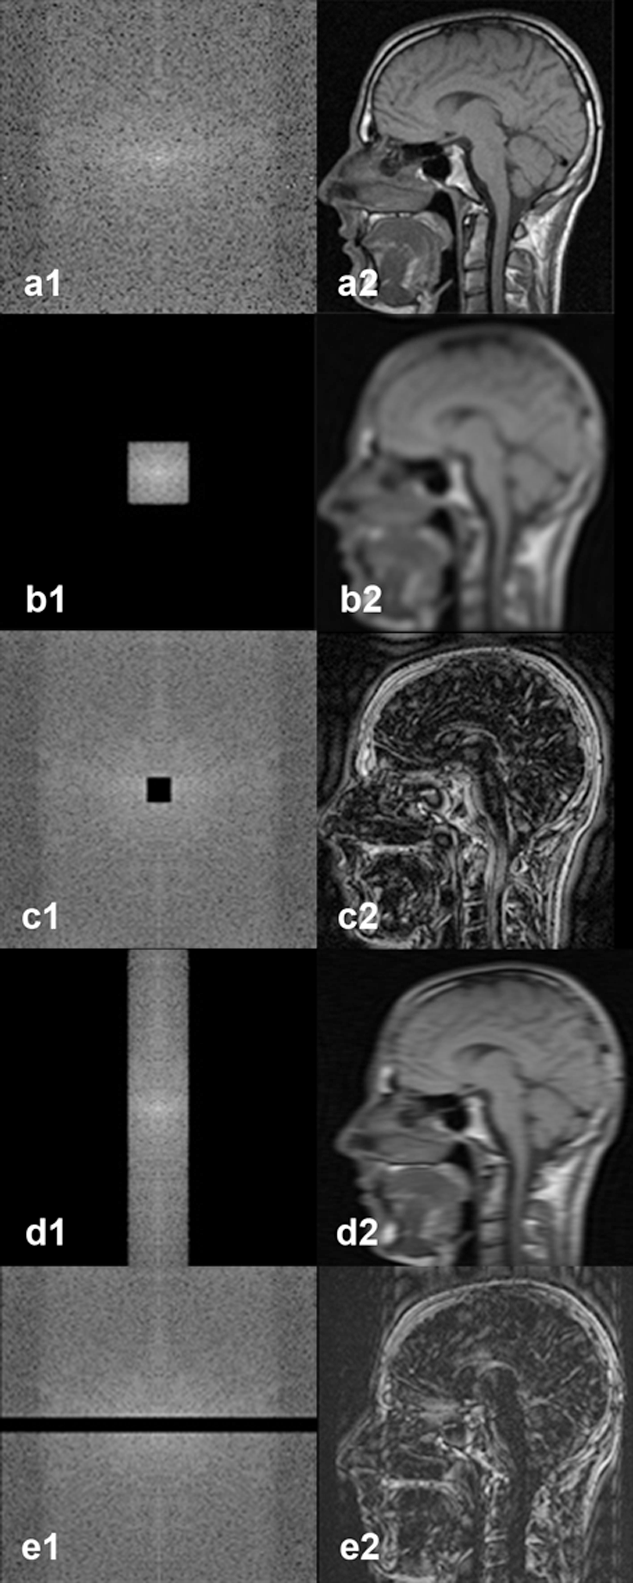

Figure 07-07:

k-Space with spatial frequency filtering.

a1|a2: Regular k-space with image re­con­struc­tion.

b1|b2: Same k-space as in (a) with filtering of the high frequencies; the reconstructed image has lost sharpness, it looks blurred, yet image contrast has hardly been affected.

c1|c2: Spatial frequency fil­te­ring of the low frequencies; the re­con­struc­ted image has lost image contrast, but image details have hardly been affected.

d1|d2: Low pass filtering in the readout direction, …

e1|e2: … high pass filtering in the preparation direction.